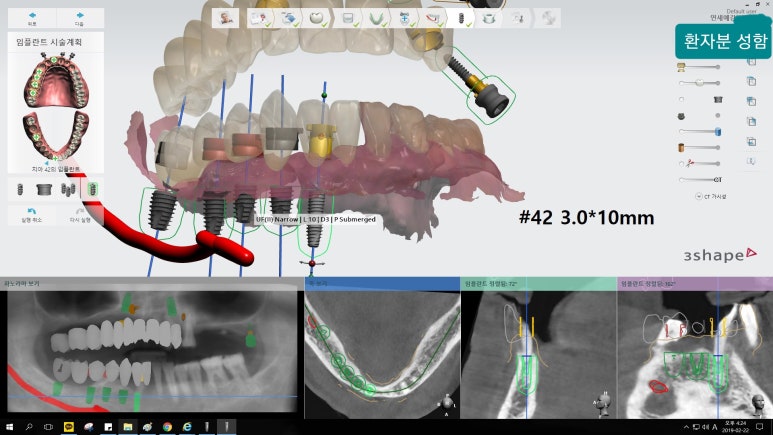

더 정확하고 안전한 임플란트식립을 위한

네비게이션임플란트

오른쪽:시술오차 가능성이 적은 내비게이션임플란트

시청역 연세예감치과에서 실제 시행한 내비게이션임플란트에 대한 모의시술사진